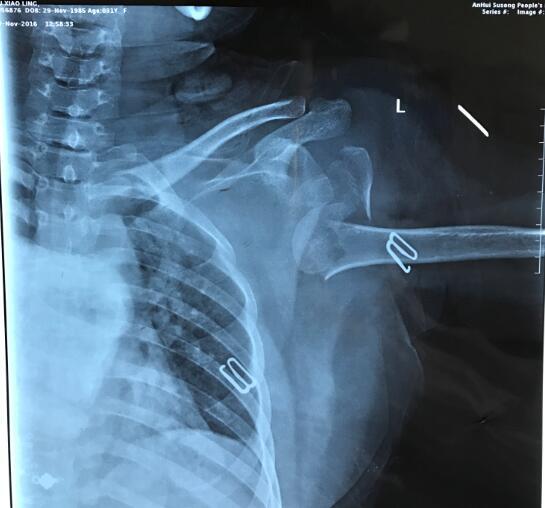

近日,我院关节与显微修复外科利用锁定钢板固定联合同种异体腓骨髓内移植成功治疗一例复杂肱骨近端骨折患者。该患者为31岁,女性,左肩车祸伤。术前射片诊断为左侧肱骨近端骨折(Neer’s四部分骨折)。我科胡孔足主任术前结合患者病史,体检及辅助检查,制定了详实的手术方案,手术顺利,术后患者恢复满意。据悉,利用锁定钢板固定联合同种异体腓骨髓内移植治疗肱骨近端骨折为安徽省首例,标志着我院在复杂肱骨近端骨折修复重建治疗上迈出坚实一步。

四部分肱骨近端骨折骨折复位后遗留严重骨缺损,术后易发生螺钉松动,肱骨头再移位、内翻移位等并发症,通常采用关节置换术治疗。由于人工关节有一定使用寿命,对于年轻患者,受到一定限制。联合引用同种异体腓骨髓内固定,能够使肱骨头获得有效支撑,内侧柱得到加强,并增加肱骨近端骨量,使锁定钢板固定更加稳定,允许患者早期功能锻炼。该技术在国外有4-5年使用经验,国内少数医院已经开展,安徽省属于首例。